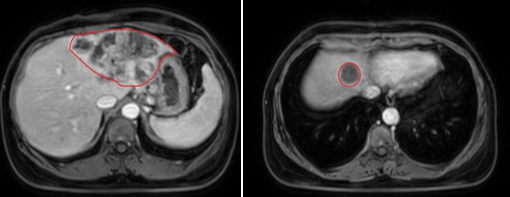

- Chụp cộng hưởng ổ bụng: Nhu mô gan hạ phân thùy II, III, IV, VIII có vài khối, kích thước lớn nhất 120x67 mm, bờ không đều ranh giới không rõ, co kéo bờ gan lân cận, tăng tín hiệu trên T2W hạn chế khuếch tán trên DWI/ADC, sau tiêm ngấm thuốc không đồng nhất thì động mạch. Vùng rốn gan đầu tụy có vài hạch, hạch lớn nhất kích thước 26x13mm.

Hình 1. Hình chụp MRI: Hình ảnh Nhu mô hạ phân thùy hạ phân thùy II, IV, VIII có vài khối .Nhu mô gan hạ phân thùy II, III, IV, VIII có vài khối, kích thước lớn nhất 120x67 mm, bờ không đều ranh giới không rõ, co kéo bờ gan lân cận(viền màu đỏ)